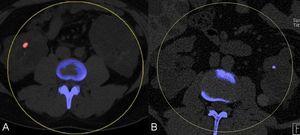

A pesar de que la EPQH es generalmente asintomática, algunos pacientes suelen experimentar complicaciones agudas o crónicas. Las complicaciones agudas más frecuentes de la EPQH incluyen infección y hemorragia intraquística. La infección quística suele presentarse con dolor localizado, fiebre, leucocitosis, velocidad de sedimentación elevada y, a menudo, fosfatasa alcalina elevada. Generalmente es monomicrobiana y causada por enterobacteriáceas. Una TC o una RM suelen diferenciar entre una infección o una hemorragia (figura 8 A y B). La tomografía por emisión de positrones con 18-fluorodesoxiglucosa (TEP-FDG) puede ser de gran utilidad en la identificación de quistes infectados en hígados poliquísticos (figura 9). Las complicaciones crónicas se deben generalmente a un agrandamiento masivo del hígado o a un efecto de masa debido a un quiste único dominante o a un grupo limitado de quistes. Los síntomas más frecuentes debidos al efecto de masa incluyen disnea, saciedad precoz, reflujo gastroesofágico y dolor lumbar mecánico. Otras complicaciones causadas por el efecto masa incluyen obstrucción del flujo eferente venoso hepático, compresión de la vena cava inferior, compresión de la vena porta o compresión del conducto biliar, que se manifiesta como ictericia obstructiva.

Figura 9. Imagen de tomografía por emisión de positrones con 18-fluorodesoxiglucosa (TEP-FDG) que demuestra una intensa captación circular de FDG en la pared de un quiste hepático, lo que sugiere una infección intraquística.